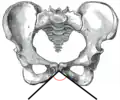

The subpubic angle (or pubic angle) is the angle in the human body as the apex of the pubic arch, formed by the convergence of the inferior rami of the ischium and pubis on either side. The subpubic angle is important in forensic anthropology, in determining the sex of someone from skeletal remains. A subpubic angle of 50–82 degrees indicates a male; an angle of 90 degrees indicates a female.[2] Other sources operate with 50–60 degrees for males and 70–90 degrees in females.[1] Women have wider hips, and thus a greater subpubic angle, in order to allow for child birth.

Female subpubic angle

Female subpubic angle Male subpubic angle

Male subpubic angle